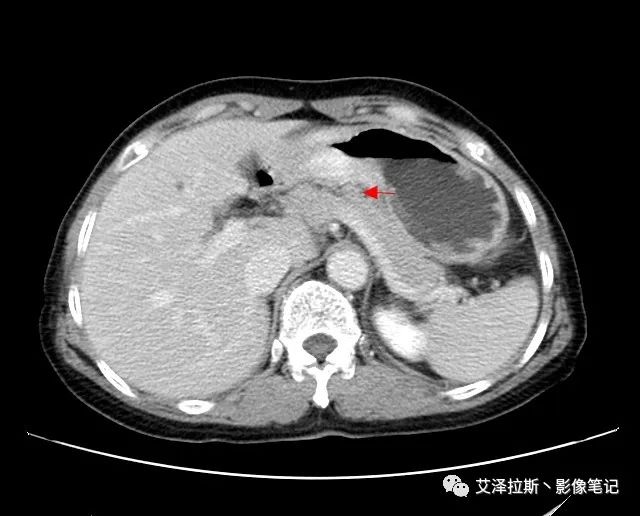

以下為累及的區(qū)域淋巴結(jié),共計15個區(qū)域:

【影像所見】 胃竇部狹窄,胃壁環(huán)形增厚,小彎側(cè)見一巨大潰瘍,周圍伴“環(huán)堤征”,漿膜面不完整,胃周脂肪見網(wǎng)格狀條索影,病灶與肝臟左葉、胰腺鉤突脂肪間隙消失,增強(qiáng)掃描病灶明顯強(qiáng)化。引流區(qū)內(nèi)約15個區(qū)域淋巴結(jié)受累。

【診斷意見】 胃竇部胃癌(T4N3期) 該病例腫塊突破漿膜層,與肝臟左葉、胰腺鉤突分界不清,脂肪界面消失,定為T4期; 受累及的淋巴結(jié)為15個區(qū)域,定為N3; 有無遠(yuǎn)處轉(zhuǎn)移尚不明確,所以M期暫時無法確定。